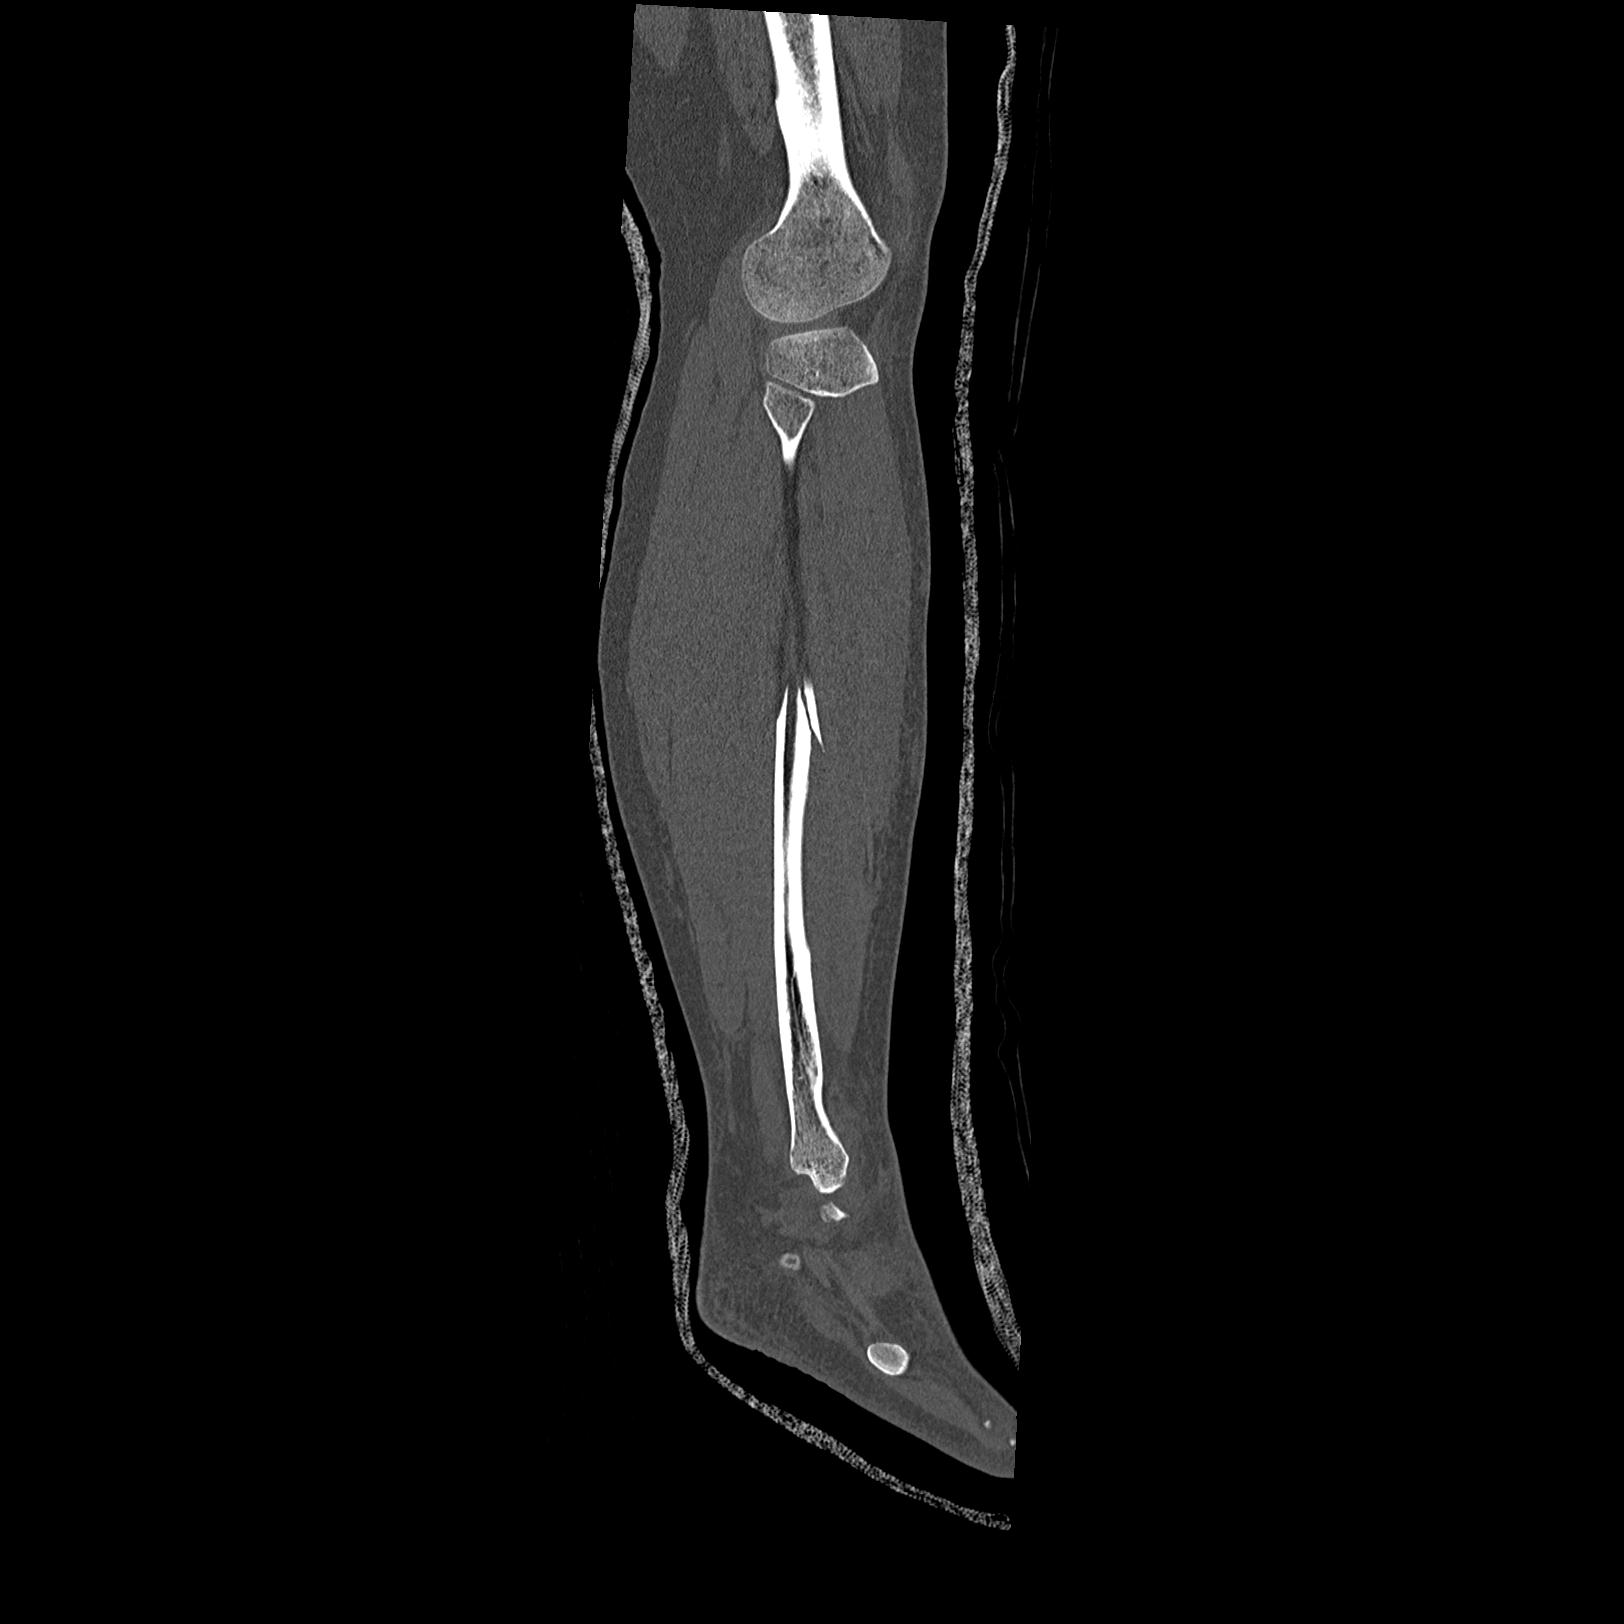

102803 1/12(キウスなし) 1/27 左下腿 4R 30歳女性 左脛骨軸内釘